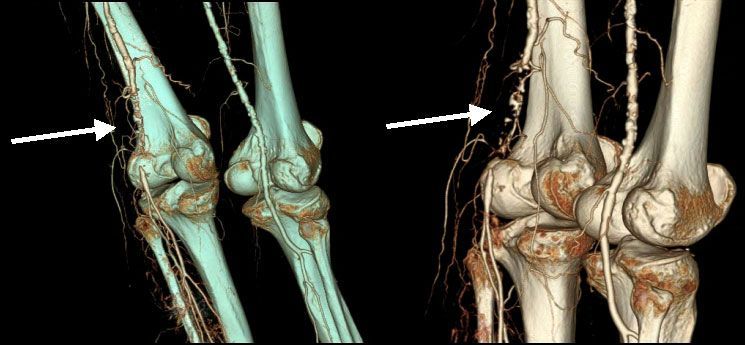

IV. Периферические артерии верхних и нижних конечностей.

Клиника поражения периферических артерий, особенно при сахарном диабете, осложненном диабетической ангиопатией – это показание для направления на МСКТ. Следующая группа пациентов - это курильщики со стажем. Доказано прямое повреждение эндотелия сосудистой стенки при курении табака, поэтому частота облитерирующих заболеваний артерий у таких больных значительно выше. Результаты исследования помогут врачу в выборе проводимой терапии, в том числе малоинвазивного эндохирургического способа лечения.

![]() |

| Рис.15-16. 3-D реконструкция периферических артерий при МСКТ. Окклюзия левой подколенной артерии (стрелка). Множественные атеросклеротические поражения, правой бедренной и правой подколенной артерии. |